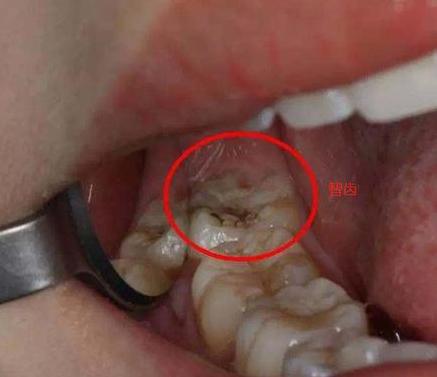

4,导致第二磨牙发生龋坏。

如果萌出的智齿的阻生智齿,尤其是水平阻生,其牙冠是抵到前面的第二磨牙的。这样的话会有一个较大的空隙,容易滞留食物残渣滋生细菌,容易引发炎症,也容易使得前面的第二磨牙龋坏。